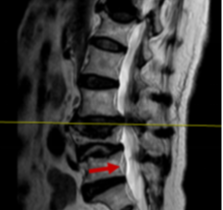

箭头所示病灶位置

然而病情并没有家属想象中简单,检查结果显示梁婆婆右侧耻骨上下支骨折、腰椎椎管狭窄,却未发现胸腰椎新鲜压缩骨折。经冯学烽主任、杨立进主治医师查体发现,婆婆还伴有臀、腿麻木症状。

冯学烽主任表示,综合检查结果和临床症状,考虑梁婆婆是摔倒后椎管压迫脊髓加重损伤,单纯治骨盆骨折无法解决行走问题,需要做传统的腰椎的开放减压内固定手术才能从根本上解决问题。